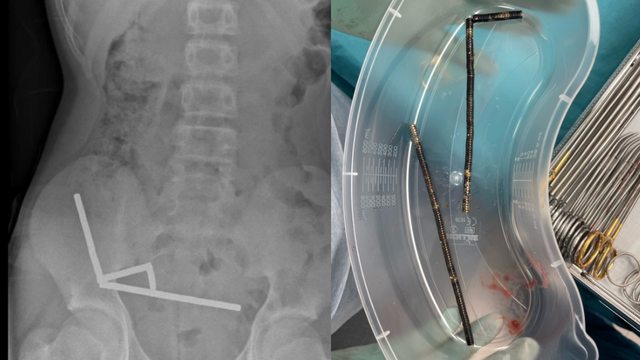

The boy ate between 80 and 100 magnets, which he said had been purchased from an online retailer.